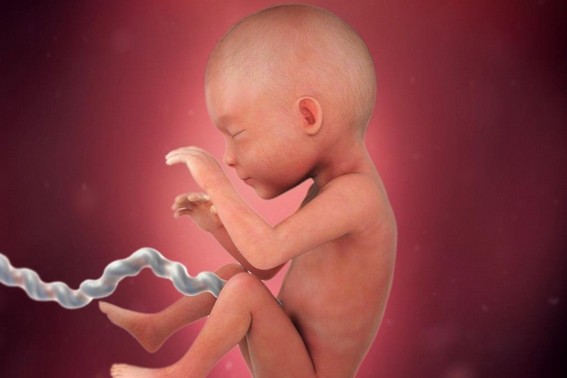

الأسبوع السابع والعشرون

خلال هذا الأسبوع يبدأ شكل الجنين بالوضوح ويصبح قريباً للشكل الذي يظهر به الجنين عند الولادة، ولكن مع اختلاف أنه صغير الحجم كما أ هناك بعض الأعضاء لم يكتمل نموها بعد مثل الرئتين والكبد، جدير بالذكر أن هناك حالات معينة يولد فيها الطفل خلال هذا الأسبوع ويعيش بشكل طبيعي جداً إذا تم الاهتمام والعناية به من قبل الأطباء بعد ولادته.